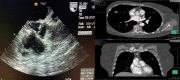

Difficult diagnosis is due to rarity of the case. TT or TE echocardiography is sufficient to make a correct diagnosis. The risk of embolism or coronary ostia occlusion should guide the decision for surgery.